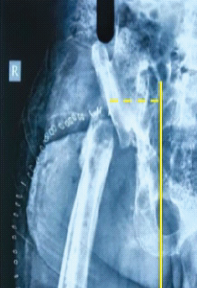

Aneurysmal Bone Cyst Presenting as a Pathological Subtrochanteric Femur Fracture in an Adolescent: A Case Report

Chandrashekhar R Rai , Sandeep V Gavhale , Vijaysing Chandele , Alok P Yadav , Chinmay S Torne , Vishal B Karpe

………………………………p.89-93